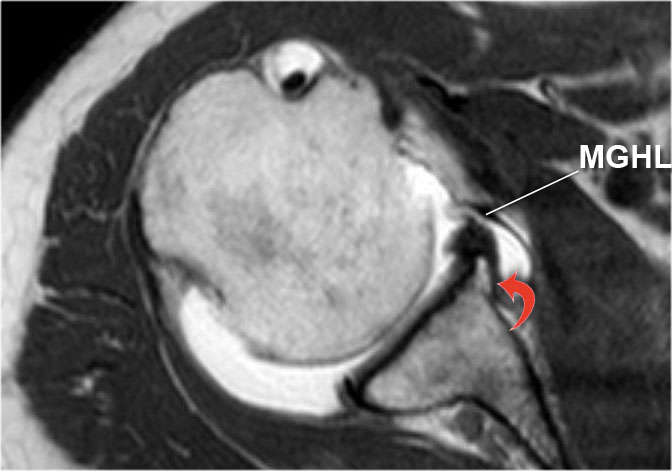

Có tổn thương Bankart xương (mũi tên đỏ cong).

Đường rách lan lên trên (mũi tên đen).

Ngoài ra còn có khuyết Hill-Sachs (mũi tên đỏ).